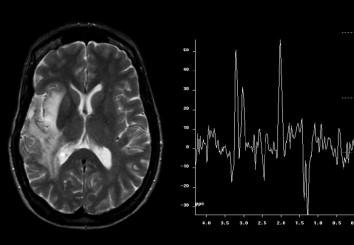

5. Chụp cộng hưởng từ phổ não là gì?

Chụp cộng hưởng từ phổ sọ não là một kỹ thuật mới được sử dụng trong chẩn đoán bệnh lý thần kinh, giúp phát hiện các chất chuyển hóa đặc hiệu của tổn thương sọ não. Chụp cộng hưởng từ phổ sọ não dựa trên nguyên lý so sánh nồng độ các chất chuyển hóa trong vùng thăm khám để xác định bản chất tổn thương.

Kết quả hình ảnh của chụp cộng hưởng từ phổ sọ não thường được phân tích thành dạng biểu đồ phổ, đặc trưng bởi thông tin tần số, chiều cao, độ rộng, diện tích, chiều cao hoặc diện tích vùng bên dưới đỉnh thể hiện nồng độ của các chất chuyển hóa. Các chất chuyển hóa phổ biến thường được ghi hình trên phổ là Choline, Creatine, NAA và Lactate. Chụp nhiều lần có thể giúp theo dõi các thay đổi về nồng độ các chất chuyển hóa, từ đó đưa ra kết luận chẩn đoán chính xác hơn.

7. Vai trò của chụp phổ não với chẩn đoán sa sút trí tuệ .

Hình ảnh chụp phổ não thu được có vai trò quan trọng trong đánh giá bệnh nhân nghi ngờ sa sút trí tuệ. Việc phát hiện những tổn thương càng sớm thì việc điều trị càng có hiệu quả. Khi thực hiện kỹ thuật, người bệnh nên tuân thủ các hướng dẫn của bác sĩ để đạt hiệu quả chẩn đoán cao, đưa ra hướng điều trị phù hợp.